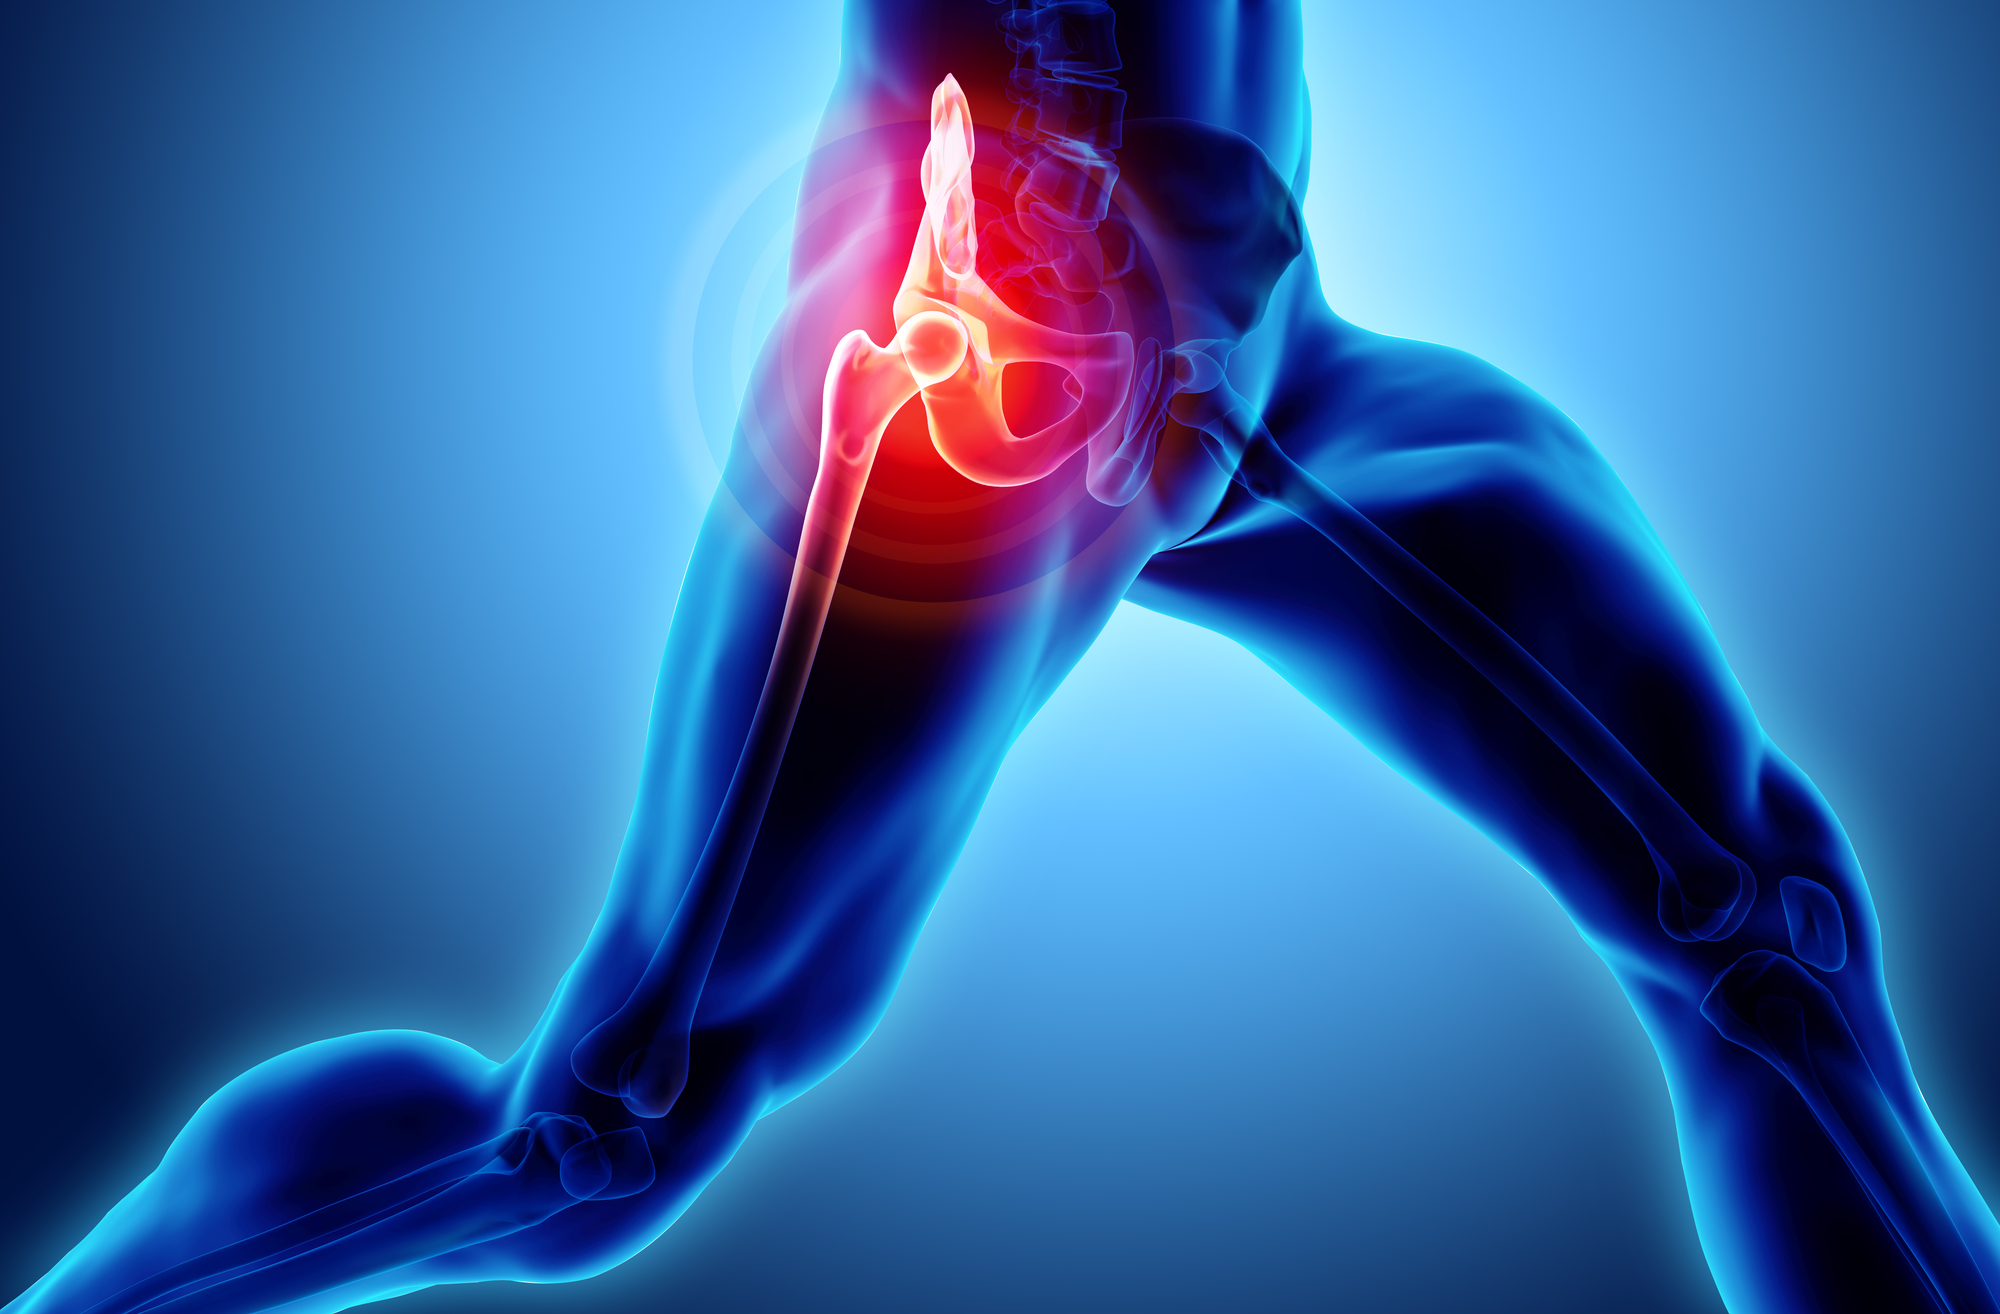

Introduction to Hip Replacement Surgery

Hip replacement surgery, also known as hip arthroplasty, is a medical procedure designed to alleviate pain and improve mobility for individuals suffering from hip joint issues. This surgical intervention involves replacing the damaged or worn-out hip joint with an artificial one, which can significantly enhance the patient’s quality of life.